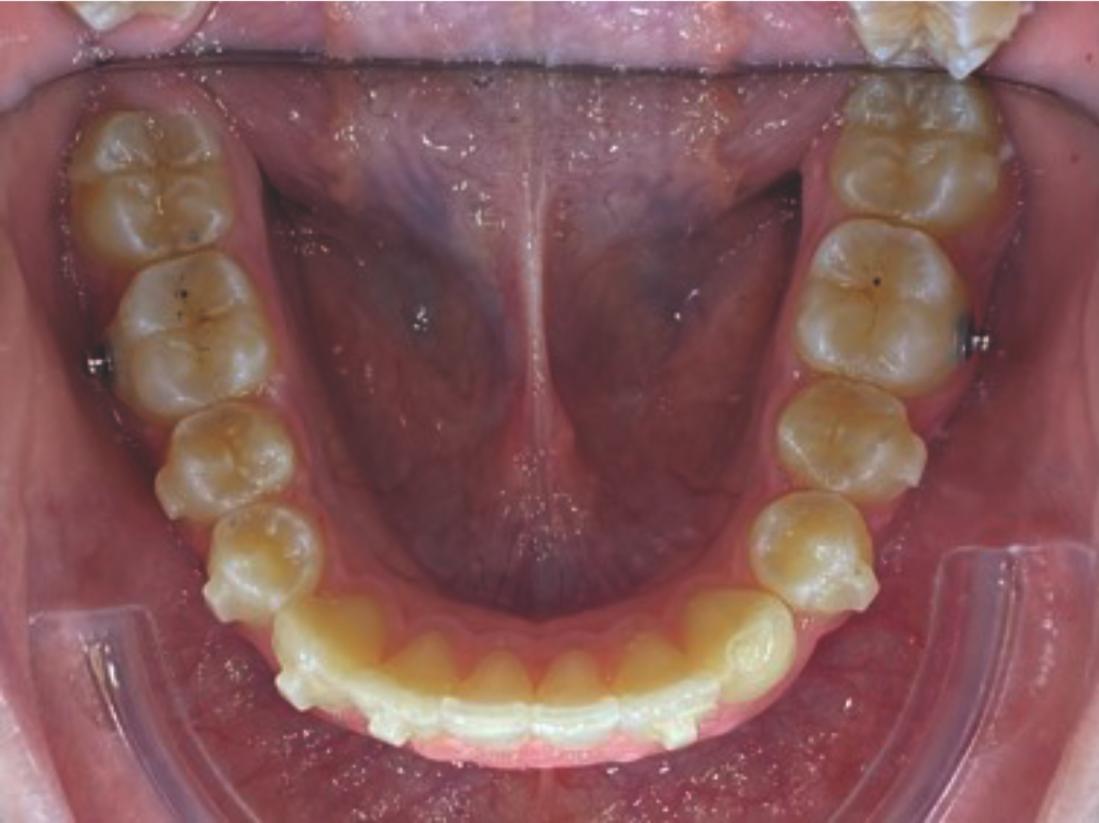

Chief complaint: We present the case of a 12-year-old female patient who came for an orthodontic evaluation, motivated by a family history of treatment. Clinical and radiographic analysis revealed a skeletal Class II malocclusion with molar and canine relationships also in Class II, moderate crowding in both arches, a deviation of the dental midline, and ectopic eruption of tooth 13. No functional issues with breathing or swallowing were observed, and oral health was generally good. A slight mandibular retrusion was noted in the soft tissue profile. A treatment plan was proposed using the Angel Aligner Pro system, aiming to correct dental misalignments and improve facial harmony through a minimally invasive, growth-adapted approach.

Clinical examination and diagnosis

- Woman ; 12/3 years

- Skeletal Class II

- Molar and canine Class II

- Upper and lower dentoalveolar compression

- Increased overjet and overbite

- Upper midline deviated 0,5 mm to the right

- Moderate upper and lower crowding